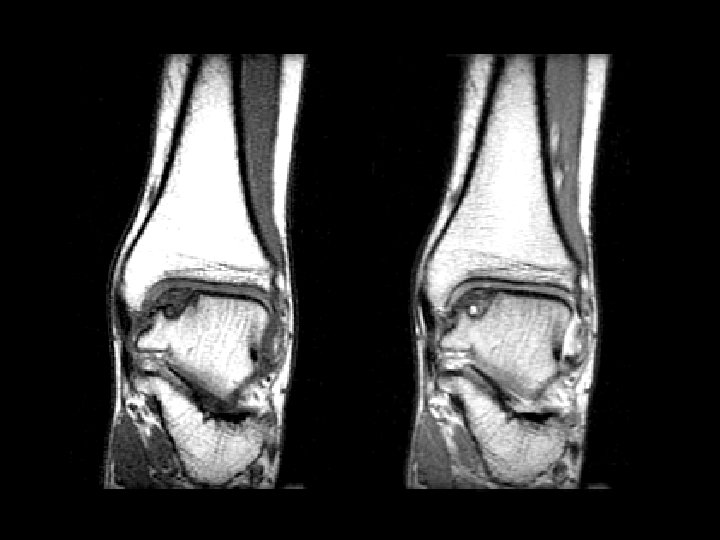

Bucket-Handle Tear • Findings: – “double PCL sign” - torn meniscus BELOW normal PCL on sag view – Above ACL on cor view – Truncation of medial meniscus – Joint effusion • Medial = 3 x lateral • Locked knee • ddx: – torn ACL, PCL – torn meniscus

Lateral Patellar Dislocation • Findings: – bone marrow edema of lateral femoral condyle and medial patella – injury of the medial patellar retinaculum – joint effusion • Patella usually dislocates laterally • Look for constellation of findings • Ddx: – NONE! – This is an Aunt Minnie